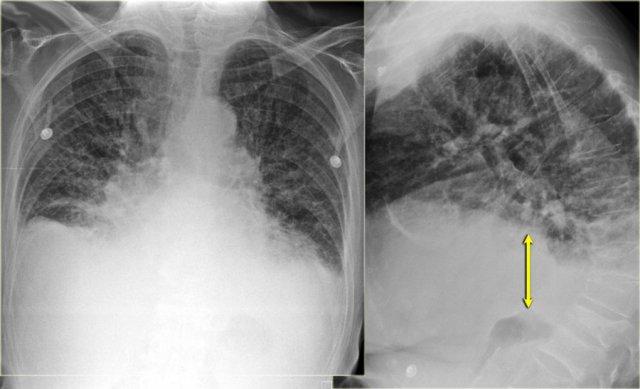

Hình ảnh bên trái là của một bệnh nhân có các dấu hiệu của suy tim sung huyết (CHF).

Thoạt nhìn, bạn có thể có ấn tượng rằng cơ hoành đang ở vị trí cao.

Tuy nhiên, khi nhận thấy khoảng cách tăng lên giữa bóng hơi dạ dày và đáy phổi, bạn sẽ nhận ra rằng có một lượng lớn dịch màng phổi ở cả hai bên (mũi tên).